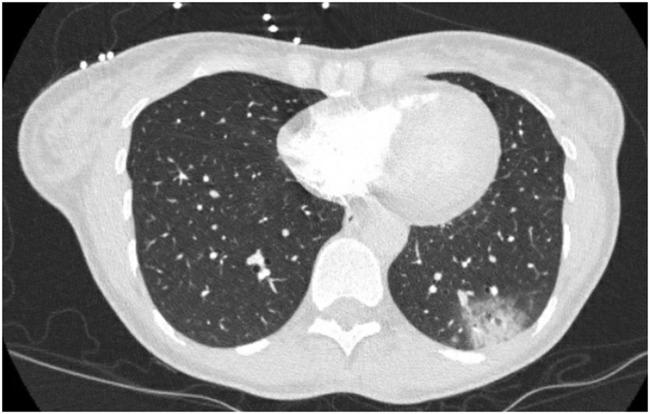

A 50 year old patient presented with bilateral lower extremity weakness, lethargy, and dyspnea. Nasopharyngeal swab was positive for SARS-CoV-2. She progressed to acute hypoxemic respiratory failure and hemodynamic instability requiring intubation, pressor support, and hemodialysis. Maculopapular rashes developed on bilateral lower extremities with progressively worsening rhabdomyolysis. Bilateral lower extremity fasciotomies were performed with subsequent serial operative debridements to remove necrotic muscle. One month later, she required a right above knee amputation. There was no evidence of macrovascular thrombosis. A high clinical suspicion of rhabdomyolysis in COVID-19 patients is necessary to avoid major limb loss.

一名50岁患者出现双侧下肢无力、嗜睡和呼吸困难。鼻咽拭子检测SARS-CoV-2呈阳性。她进展为急性低氧性呼吸衰竭和血流动力学不稳定,需要插管、血管活性药物支持和血液透析。双侧下肢出现斑丘疹,横纹肌溶解症逐渐加重。对双侧下肢进行了筋膜切开术,随后进行了一系列手术清创以清除坏死肌肉。一个月后,她需要进行右膝上截肢。没有大血管血栓形成的证据。对COVID-19患者高度怀疑横纹肌溶解症对于避免肢体严重丧失至关重要。